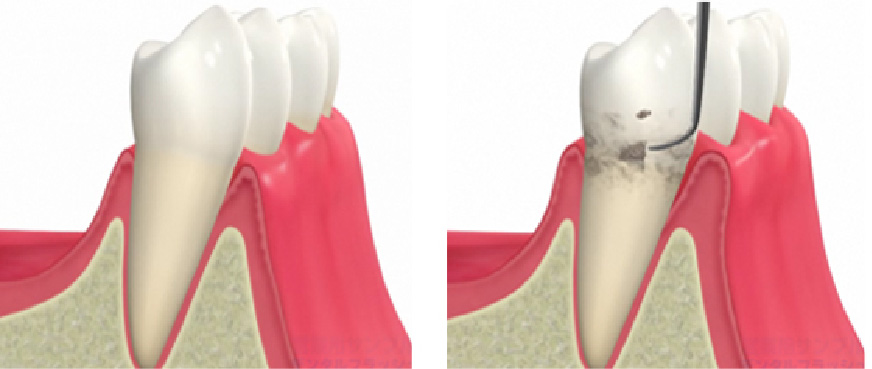

超音波チップを用いて歯周ポケット内のバイオフィルム(細菌の集合体)を除去します。歯周病菌は嫌気性菌であるため、酸素の届きにくい歯周ポケット内でバイオフィルムという形で増殖します。クリーニング後3~4ヶ月すると再びバイオフィルムが成熟し、歯周病を進める要因になってしまいます。こうした細菌を体の免疫力で抑えられる範囲にコントロールしておくことが、歯周病予防において最も重要です。歯周ポケット内のバイオフィルムはご自身の歯磨きでは除去することができません。毎日の丁寧な歯磨きやフロッシングに加え、3~6ヶ月に一度は必ずメインテナンスを受けましょう。

歯石除去

歯石が残ったままメインテナンスを行っても歯周病は進行してしまいます。レントゲン上で歯石がついている場合は、歯石除去後もレントゲンを撮影し取り残しがないか確認していきます。